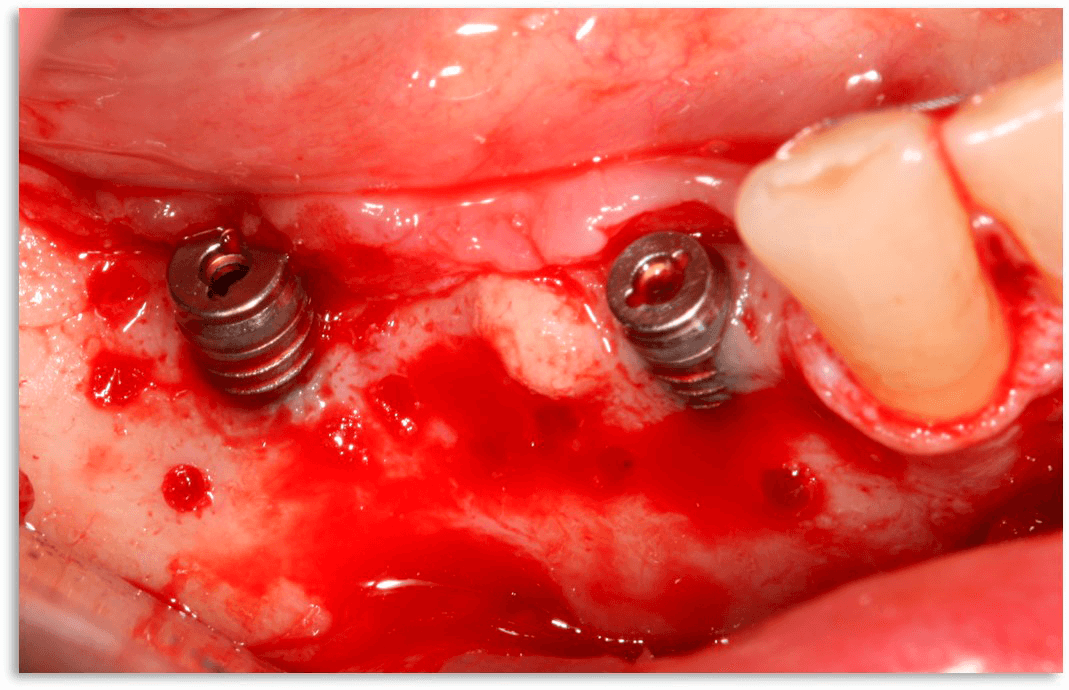

Имплантаияпри одновременном восстановлениигоризонтальных дефектов челюсти - не«сосидж»